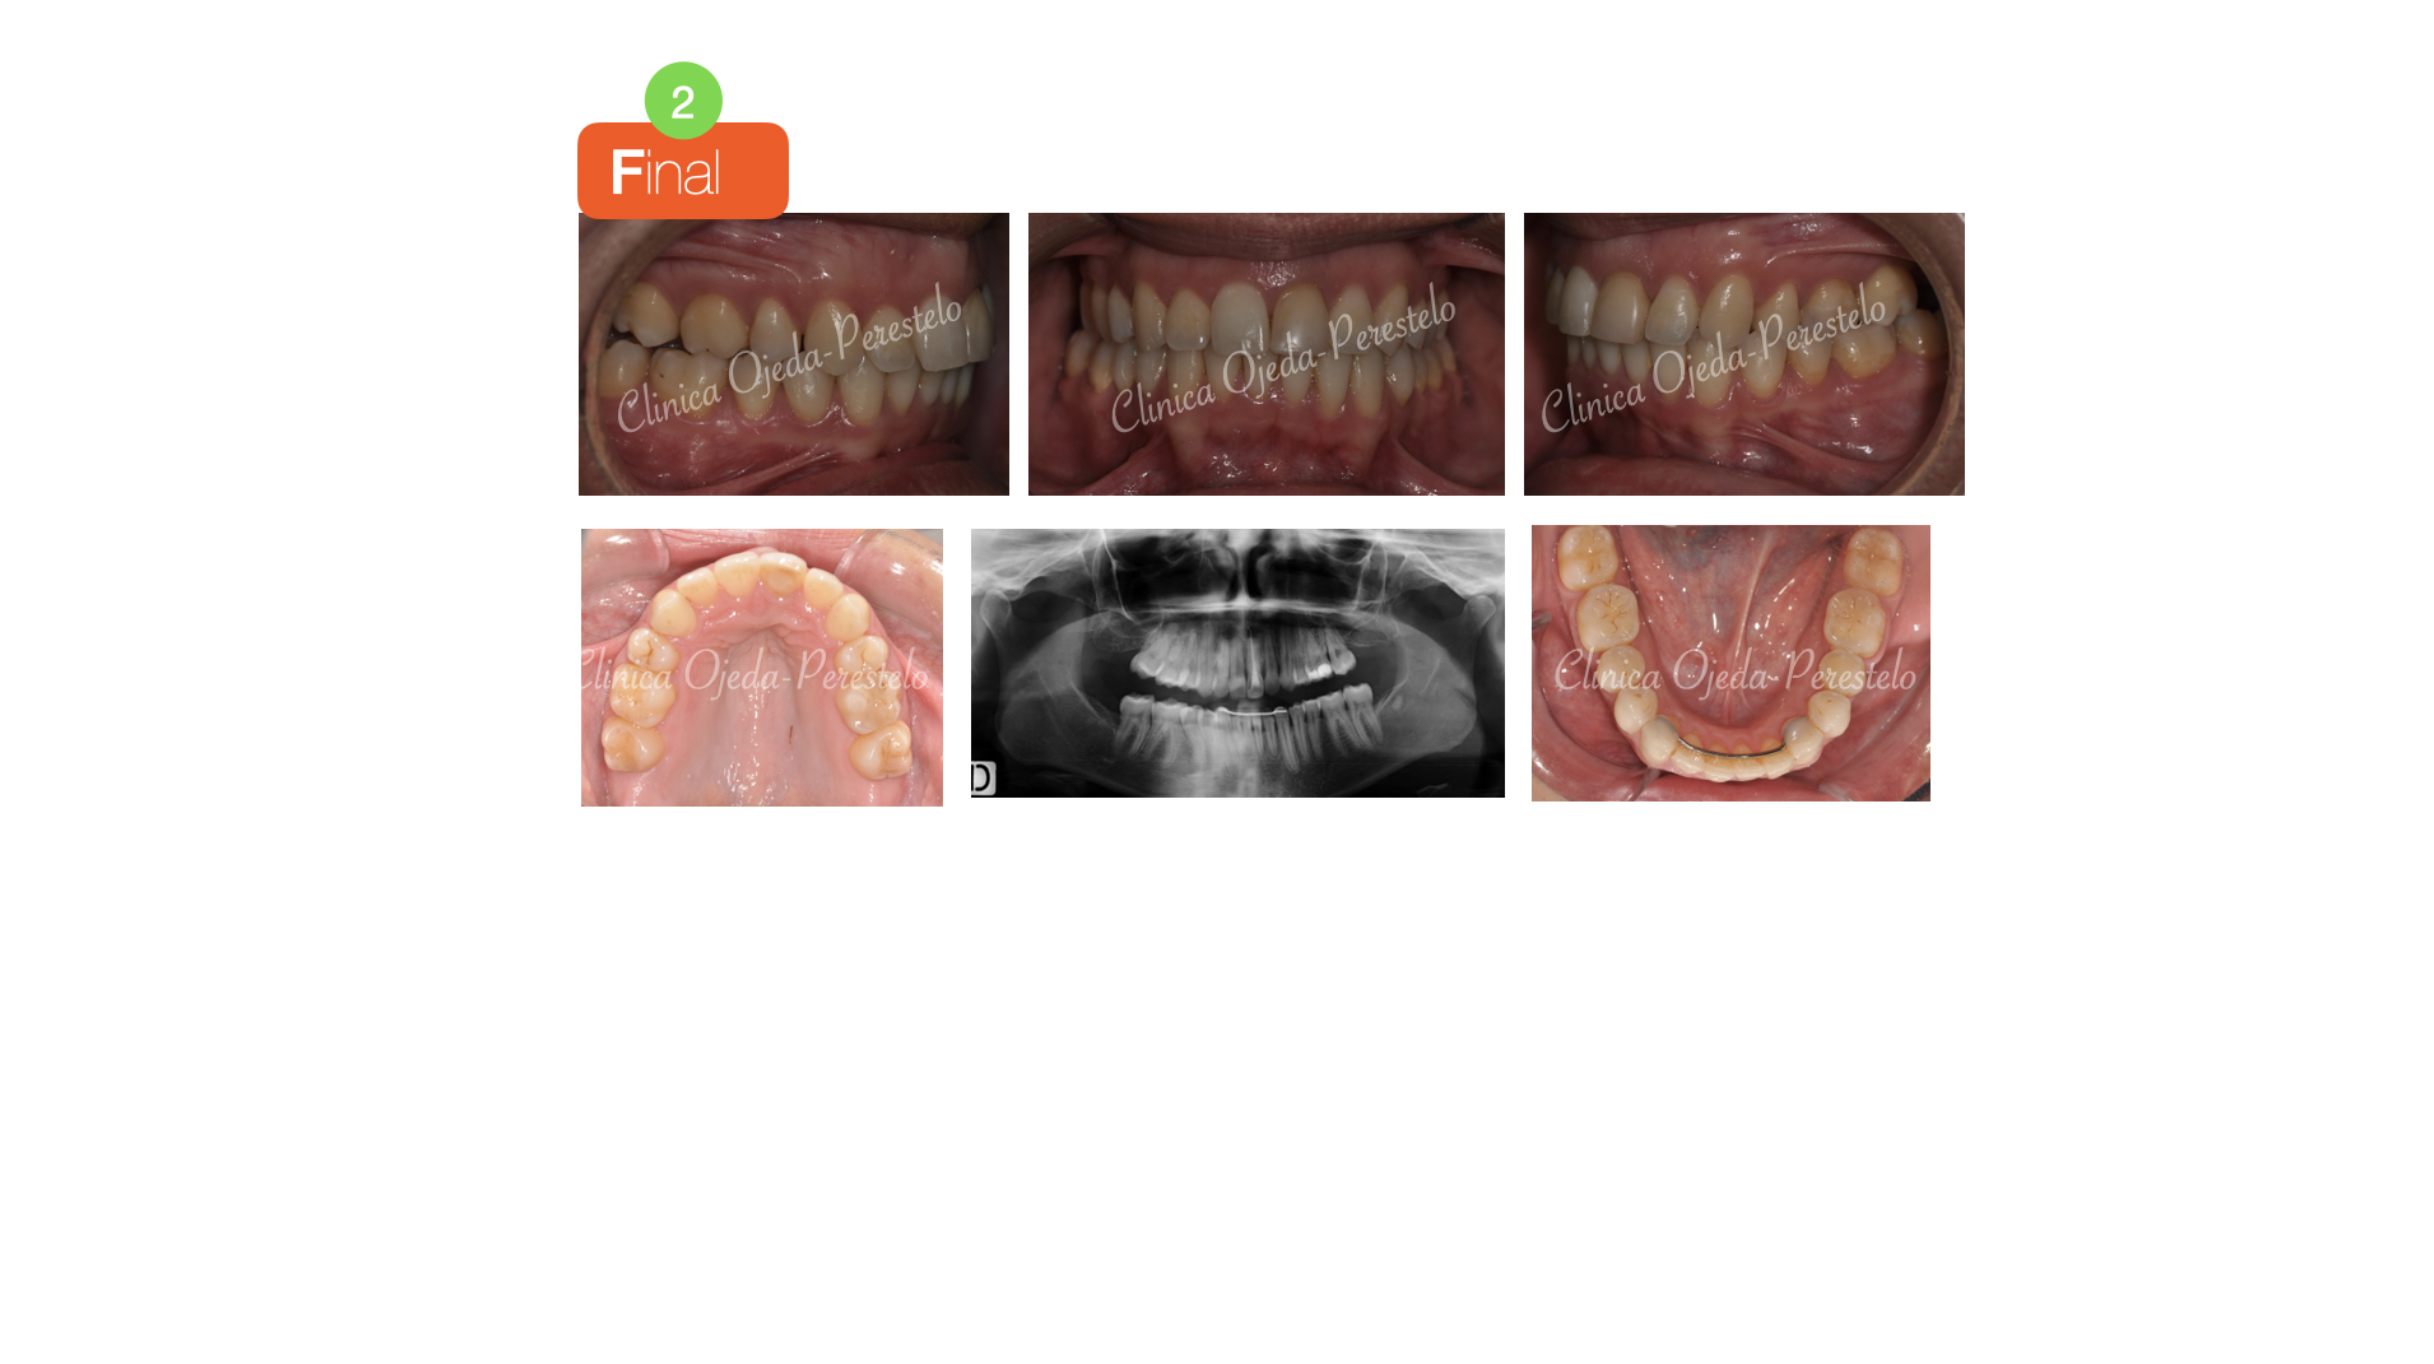

Paciente tratada con brackets de autoligado pasivo (Sistema Damon) donde hemos alineado, nivelado y expandido las arcadas. Hemos realizado las extracciones de los premolares superiores para disminuir el Resalte ya que la paciente no quería realizarse cirugía ortognática.

Quisieramos destacar cómo las extracciones de premolares no empeoran la amplitud de la sonrisa además de la mejora en la sonrisa gingival realizada con Microtornillos.